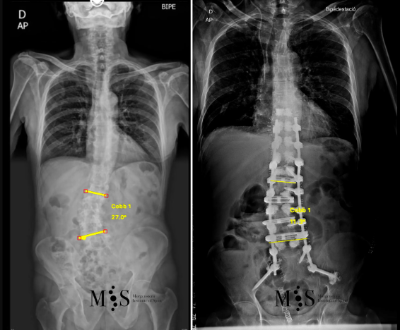

Scoliosis is a deformity/curving of the spine in the frontal plane. It can be congenital (present since birth) or degenerative (developed during the aging process). Progressive degeneration of the intervertebral disks (because of age, weight, activity, etc.) can lead to the spine to deform and curve in, ending up as a degenerative scoliosis, also called "de novo" because it is of "new" appearance in comparison to congenital scoliosis which has been present since birth.

Scoliosis lead to a curved back with the patient having problems walking with a straight back, and it can lead to an intense back pain. The spinal deformity and curving can lead to an impingement of the nerve roots which can cause radiating leg pain.

In these painful cases, surgery is indicated to (partially) correct the deformity and mainly to reduce/eliminate the pain generated by the scoliosis. In the most severe scoliosis cases an osteotomy (chiseling of a vertebral bone) may be required to straighten up the spine and reduce its deformity.

At the Morgenstern Institute of Spine we use the most advanced surgical endoscopic and percutaneous techniques to correct the degenerative scoliosis and speed up the patient’s recovery time. Hospital discharge is usually just a few days after surgery.